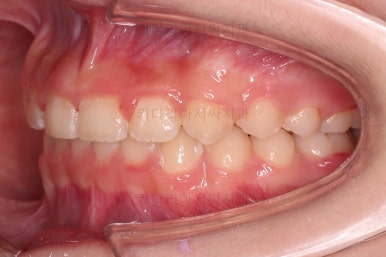

앞니의 각도가 앞으로 살아난 것이 보이실 거에요.

자연스레 과개교합 경향도 개선되어 어금니로 물렸을 때 아래 앞니가 점점 보이기 시작해요.

과개교합, 옥니, 앵글씨 2급 부정교합 모두 좋아지고 있어요.

앞니 각도가 매우 좋아졌고요.(옥니 개선) 위 아래 앞니가 덮는 정도도 개선되었어요.(과개교합, 딥바이트)

엉성했던 어금니 맞물림도 매우 좋아졌어요.(앵글씨 2급 부정교합)